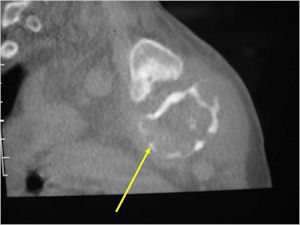

- The periosteum remains intact around the soft tissue component. Might need a CT scan to detect the subtle calcification (Egg Shell Rim of Calcification) associated with an intact periosteal reaction

- The lesion may be entirely radiolucent but usually shows some degree of mineralization. Mineralization may appear stippled like cartilage but do not see chondroid pathologically. Mineralization is sometimes better detected on a CT scan rather than an x-ray.

CT Scan:

- More useful for detecting mineralization and evaluating extent of bone destruction than plain X-ray

- Soft tissue component usually surrounded by shell of reactive bone or periosteum (Egg Shell Rim of Calcification)